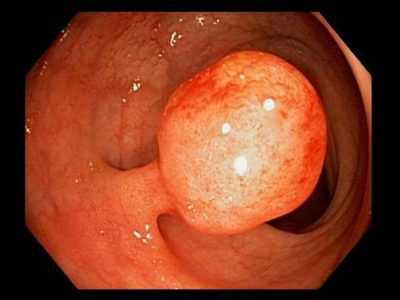

В ряде случаев полипы удается выявить уже на стадии ректального осмотра. Для оценки состояния нижних отделов кишечника и определения выраженности семейного полипоза толстой кишки осуществляют ректороманоскопию. Затем проводят колоноскопию. В процессе эндоскопических исследований обращают внимание на более крупные вишневые либо ярко-красные узлы с рыхлой либо дольчатой поверхностью (ворсинчатые полипы), поскольку для таких опухолей характерна повышенная вероятность озлокачествления.

- Железистые (аденоматозные) полипы толстой кишки. Являются самым распространенным видом полипов, обнаруживаются у половины больных. Представляют собой плотные розоватые или красноватые гиперпластические разрастания железистого эпителия, обычно грибовидной формы, реже - ветвящиеся, стелющиеся по слизистой оболочке. Средний диаметр аденоматозных полипов составляет 2-3 см. Образования не склонны к изъязвлению и кровоточивости. Могут малигнизироваться.